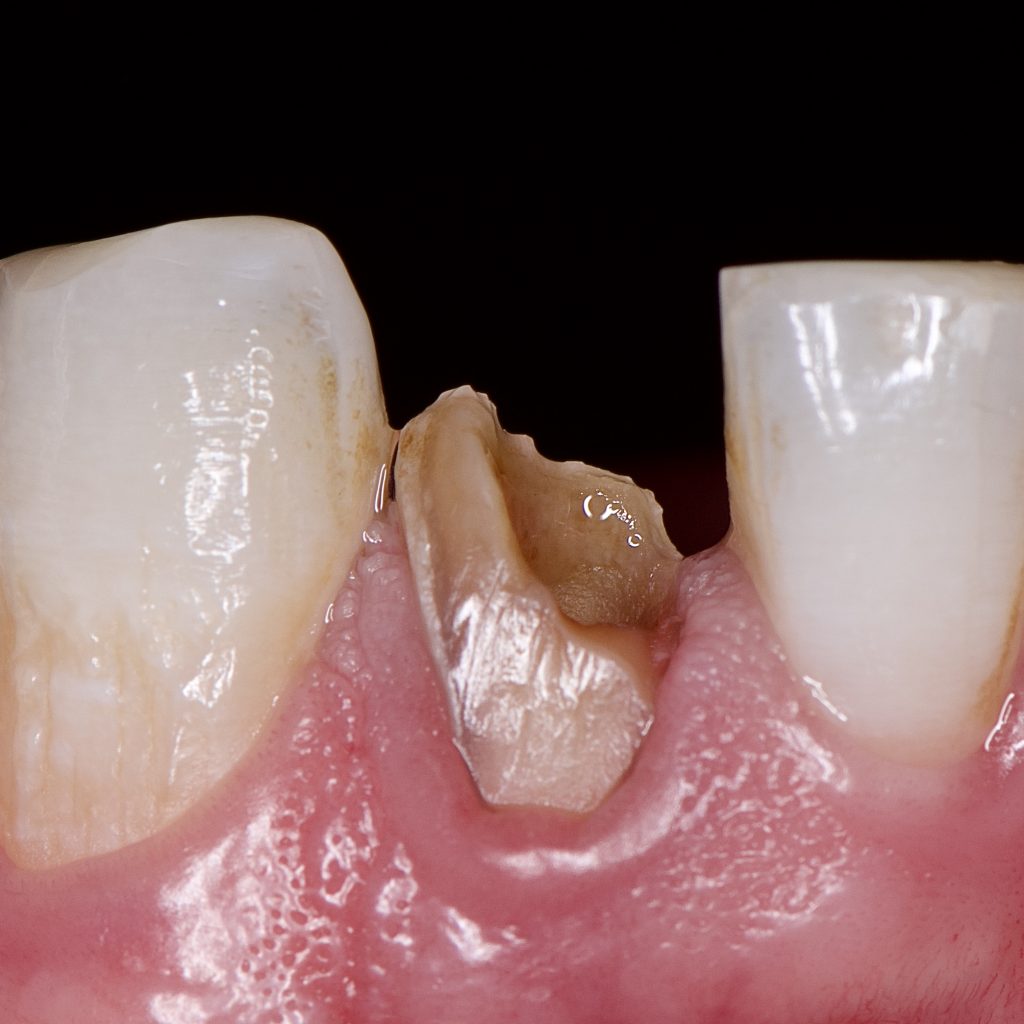

25 years old male had sport injury long period ago.

He Visited us because of pain in his fractured lower anterior tooth

Fractured Lower lateral incisor was necrotic and had periapical lesion as seen in X-ray